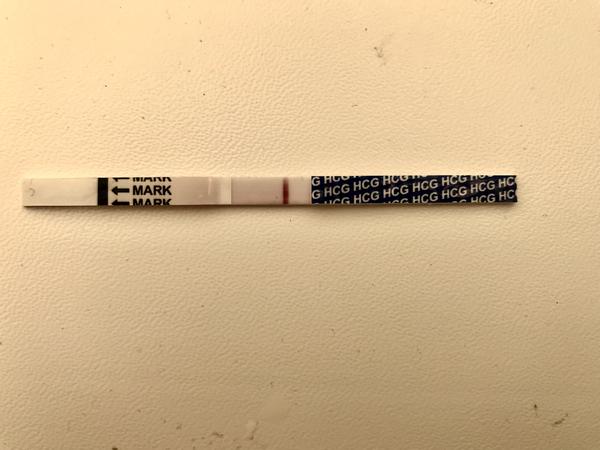

ahojte babule, mam taku otazku...mate skusenost ze pocas 3 dni vam nesilnela druha ciarka na teste ale bola rovnaka???ako duch????

@luta13 jednoznacne hodim foto co a jak..aj mne sa tak zda ze som ho tam videla. Uz neviem co mam robit dnes ma neskutocne bolelo podbrusko, bradavky su citlive na akykolvek dotyk. Takato podrazdena a celkovo citliva som nebola uz davno. A ten testik som uz vyhodila, ale chcem zajtra skusit znovu co to dá 😀